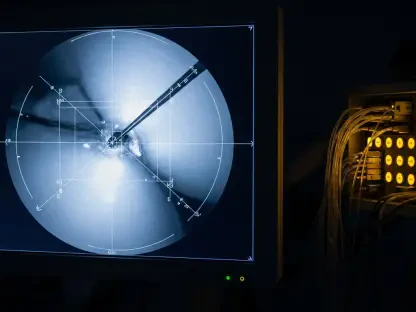

Enhanced Visualization

These robots are equipped with advanced imaging technologies that provide enhanced visualization during surgery. High-definition 3D cameras and imaging sensors allow surgeons to view the surgical field with unprecedented clarity. This level of detail aids in the precise placement of instruments, minimizing tissue damage and expediting recovery times.